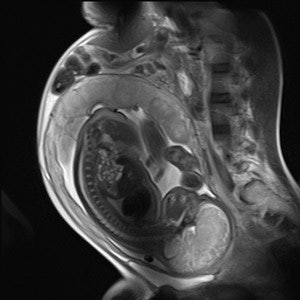

Fetal MR spectroscopy can assist with in utero measurements of fetal cerebral lactate concentrations. It may provide information on the adequacy of fetal oxygenation, and can help with decision-making on the optimal time of delivery. This figure shows fetal localizers used for spectroscopy measurements. Image courtesy of Janet De Wilde, PhD, and C. McComb."In the pre-examination questionnaire for determination of pregnancy, it is important to ask two questions: What was the first day of your last complete menstrual period? To the best of your knowledge, are you pregnant, or do you think you could be?" he said during last year's ECR refresher course on pregnancy.

In MRI, fast sequences are used to overcome image quality artifacts caused by fetal motion, and this can lead to the use of high-specification magnetic field gradients; the frequency range for the gradients is from 1 kHz to 10 kHz. The main concerns are the clinical effects of low-frequency EMF (electromagnetic fields)-induced currents and acoustic noise, but overall there is no indication the use of clinical MR procedures during pregnancy produces adverse effects, according to Janet De Wilde, PhD, executive manager of SINAPSE (Scottish Imaging Network: A Platform for Scientific Excellence) at the University of Edinburgh.

| Sagittal HASTE image used for planning further fetal images in other planes, taken at the Clinical Research Imaging Center, University of Edinburgh. Image courtesy of Janet De Wilde, PhD, and Dr. Scott Semple. |